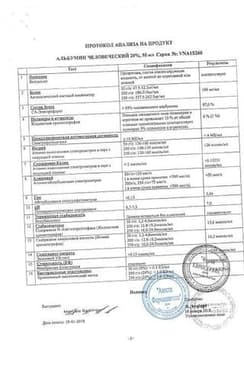

Состав препарата Альбумин

Раствор для инфузий 20% 1 мл альбумин человека 200 мг

10 мл - ампулы (10) - пачки картонные.20 мл - ампулы (10) - пачки картонные.50 мл - бутылки для кровезаменителей (1) - пачки картонные.100 мл - бутылки для кровезаменителей (1) - пачки картонные.